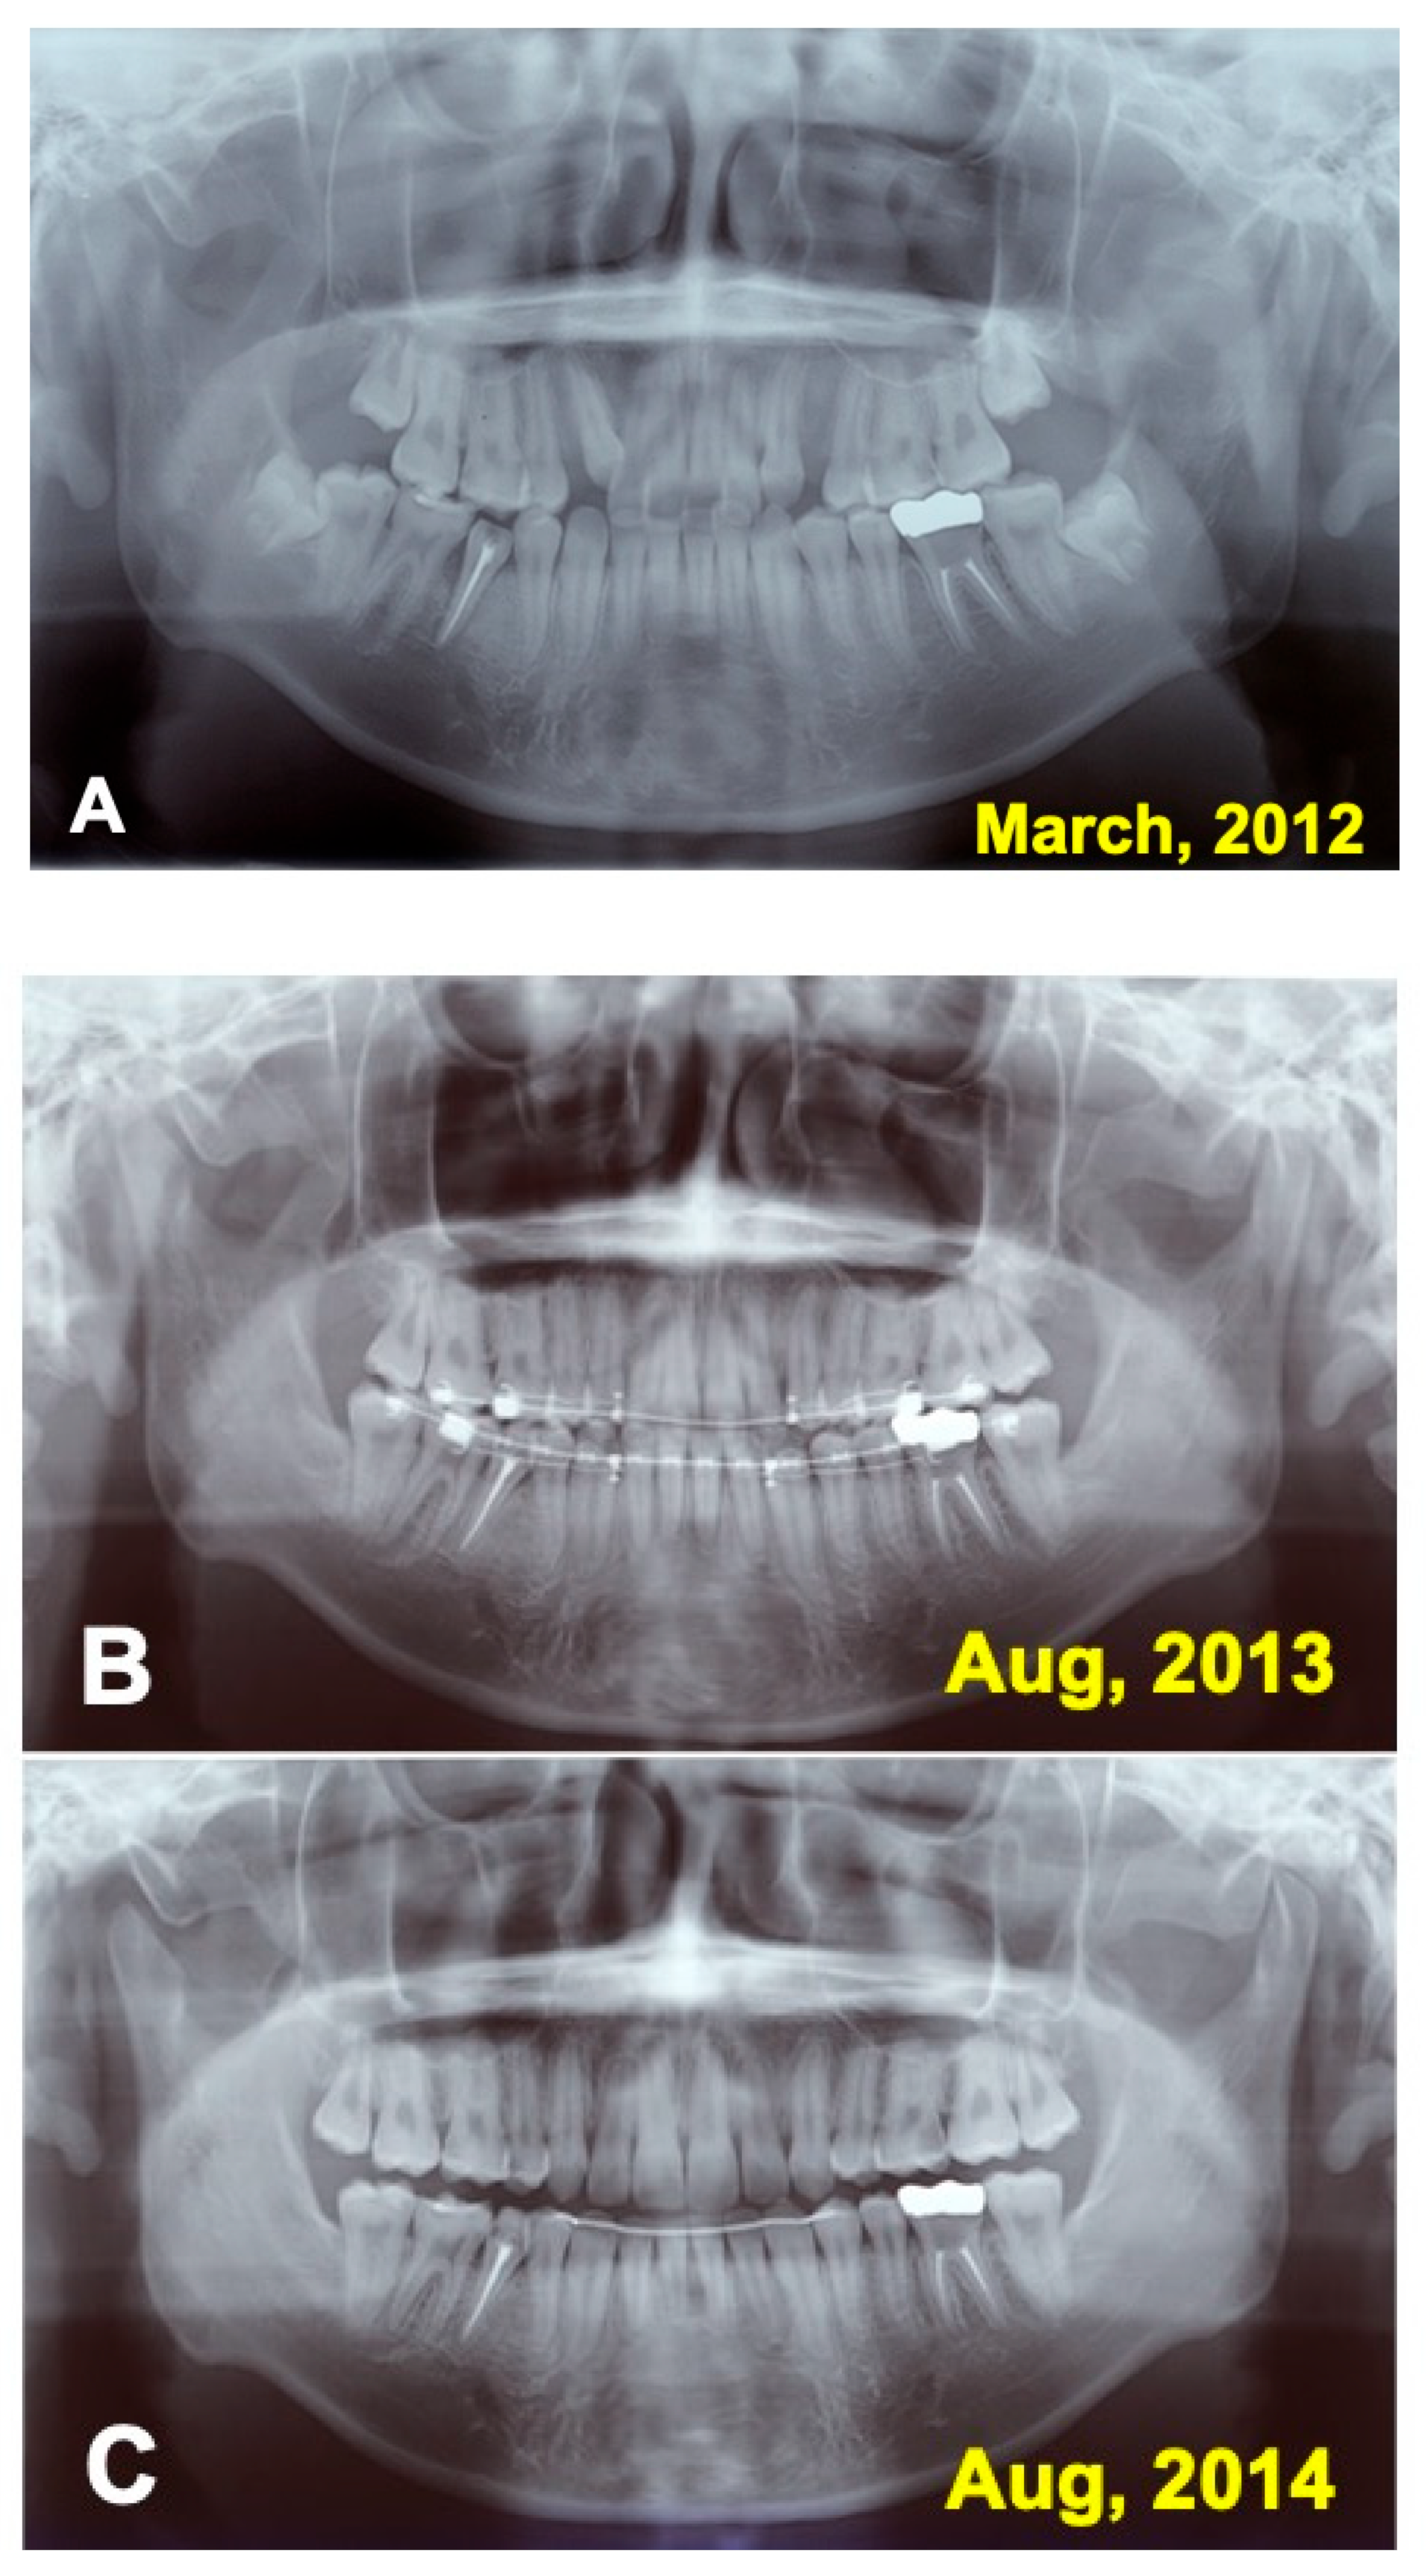

Figure 6.

Panoramic X-ray photos. (A) Appearance just after surgery. (B) Appearance at 1.5 years during orthodontic treatment. Note: extraction of wisdom teeth (#38, #48). (C) Appearance at 2.5 years. Removal of orthodontic devices, except mandibular retention wire.

Just after the surgery, the extracted sockets of the maxillary premolars and the root canal filling of the transplanted tooth were seen clearly (Figure 6A). The grafted pDDM were confirmed as each radiopaque granule (Figure 7A). The transplanted root and bone showed a similar radio-opacity, and a periodontal ligament space was not seen (Figure 6A). After 1.5 year of orthodontic treatment, the periodontal ligament space and alveolar ridge line were observed, and pDDM granules were not seen clearly (Figure 6B and Figure 7B). In addition, all wisdom teeth were already extracted (Figure 6B). A slight curve of the root surface was observed adjacent to a normal periodontal ligament space and the lamina dura during the orthodontic treatments (Figure 7B). The view at 2.5 years shows removal of orthodontic devices, except the mandibular retention wire, and a single standing of the transplanted tooth without wire (Figure 6C and Figure 7C). A continuous periodontal ligament space and lamina dura were found, and root concrescence did not occur (Figure 7C and Figure 8B).